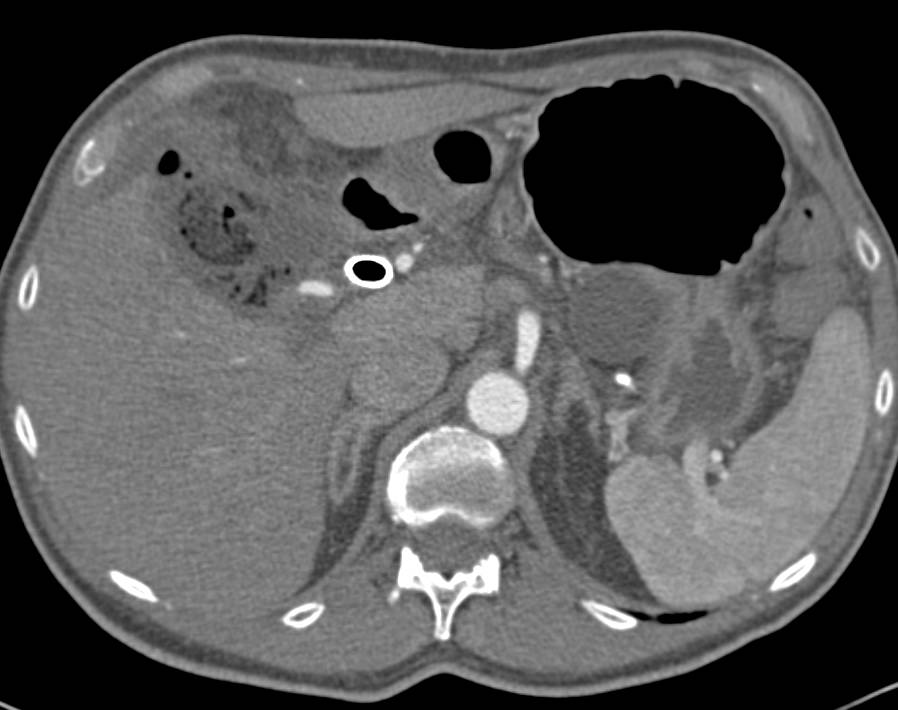

Recurrent Colon Cancer with Tumor in right Lower Quadrant Extending up to Right Kidney with Liver Metastases